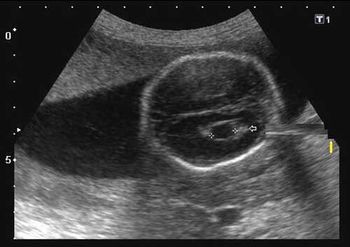

QUIZ: What is your diagnosis based on these fetal echo images?